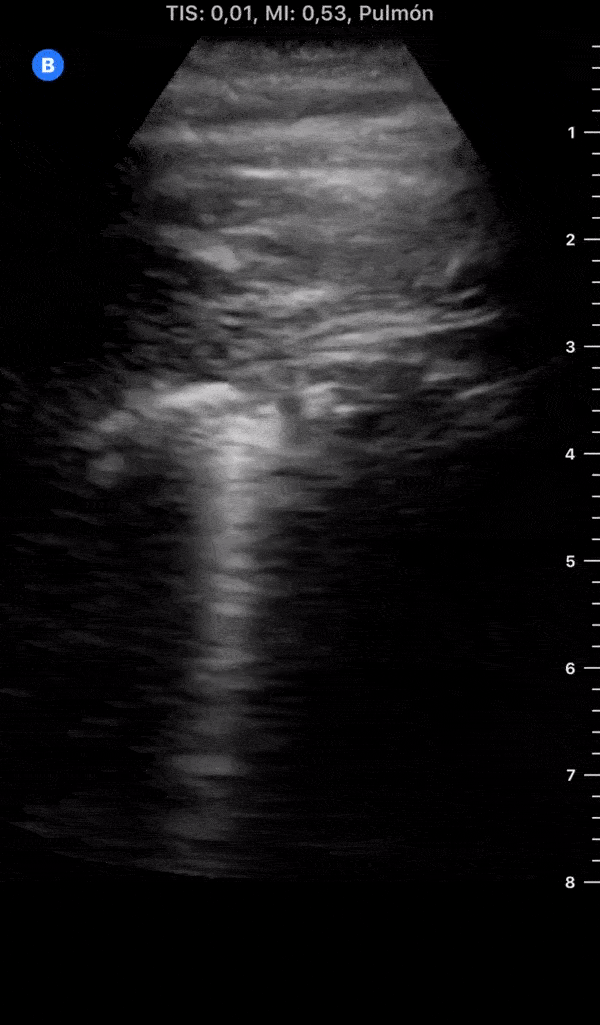

Day 4 after #COVID diagnosis. More cough & tiredness (very badly), still no dyspnea/chest pain. #POCUS update: Right side on resolution, Left side a more thickened pleural line + 2 subpleural consolidations. @yaletung